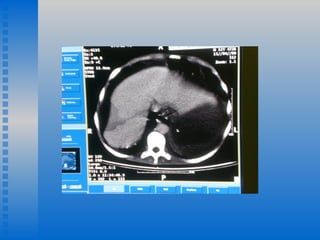

A noite do dia 14-04  o paciente evoluiu com piora da dor abdominal e hipertimpanismo acentuado Suspensa codeína e mantida analgesia com dipirona. Iniciada dimeticona regular.  15-04 D14 IH e D9 de ceftazidime e ciprofloxacina. Paciente grave com piora do estado geral, com dor intensa em todo abdome e volta da dispnéia. AR: Expansibilidade diminuída,estertores e crepitações e tiragem intercostal. Abdome doloroso e extremamente distendido. Resultado da TC de abdome: Área hipodensa,sugestiva de infarto em parênquima hepáticoD.Distensão de alça de delgado e estômago(Ascite) Isquemia Mesentérica ??  Infarto Hepático ?? Trombose Supra hepática ?/?

A noite dodia 14-04 o paciente evoluiu com piora da dor abdominal e hipertimpanismo acentuado Suspensa codeína e mantida analgesia com dipirona. Iniciada dimeticona regular. 15-04 D14 IH e D9 de ceftazidime e ciprofloxacina. Paciente grave com piora do estado geral, com dor intensa em todo abdome e volta da dispnéia. AR: Expansibilidade diminuída,estertores e crepitações e tiragem intercostal. Abdome doloroso e extremamente distendido. Resultado da TC de abdome: Área hipodensa,sugestiva de infarto em parênquima hepáticoD.Distensão de alça de delgado e estômago(Ascite) Isquemia Mesentérica ?? Infarto Hepático ?? Trombose Supra hepática ?/?